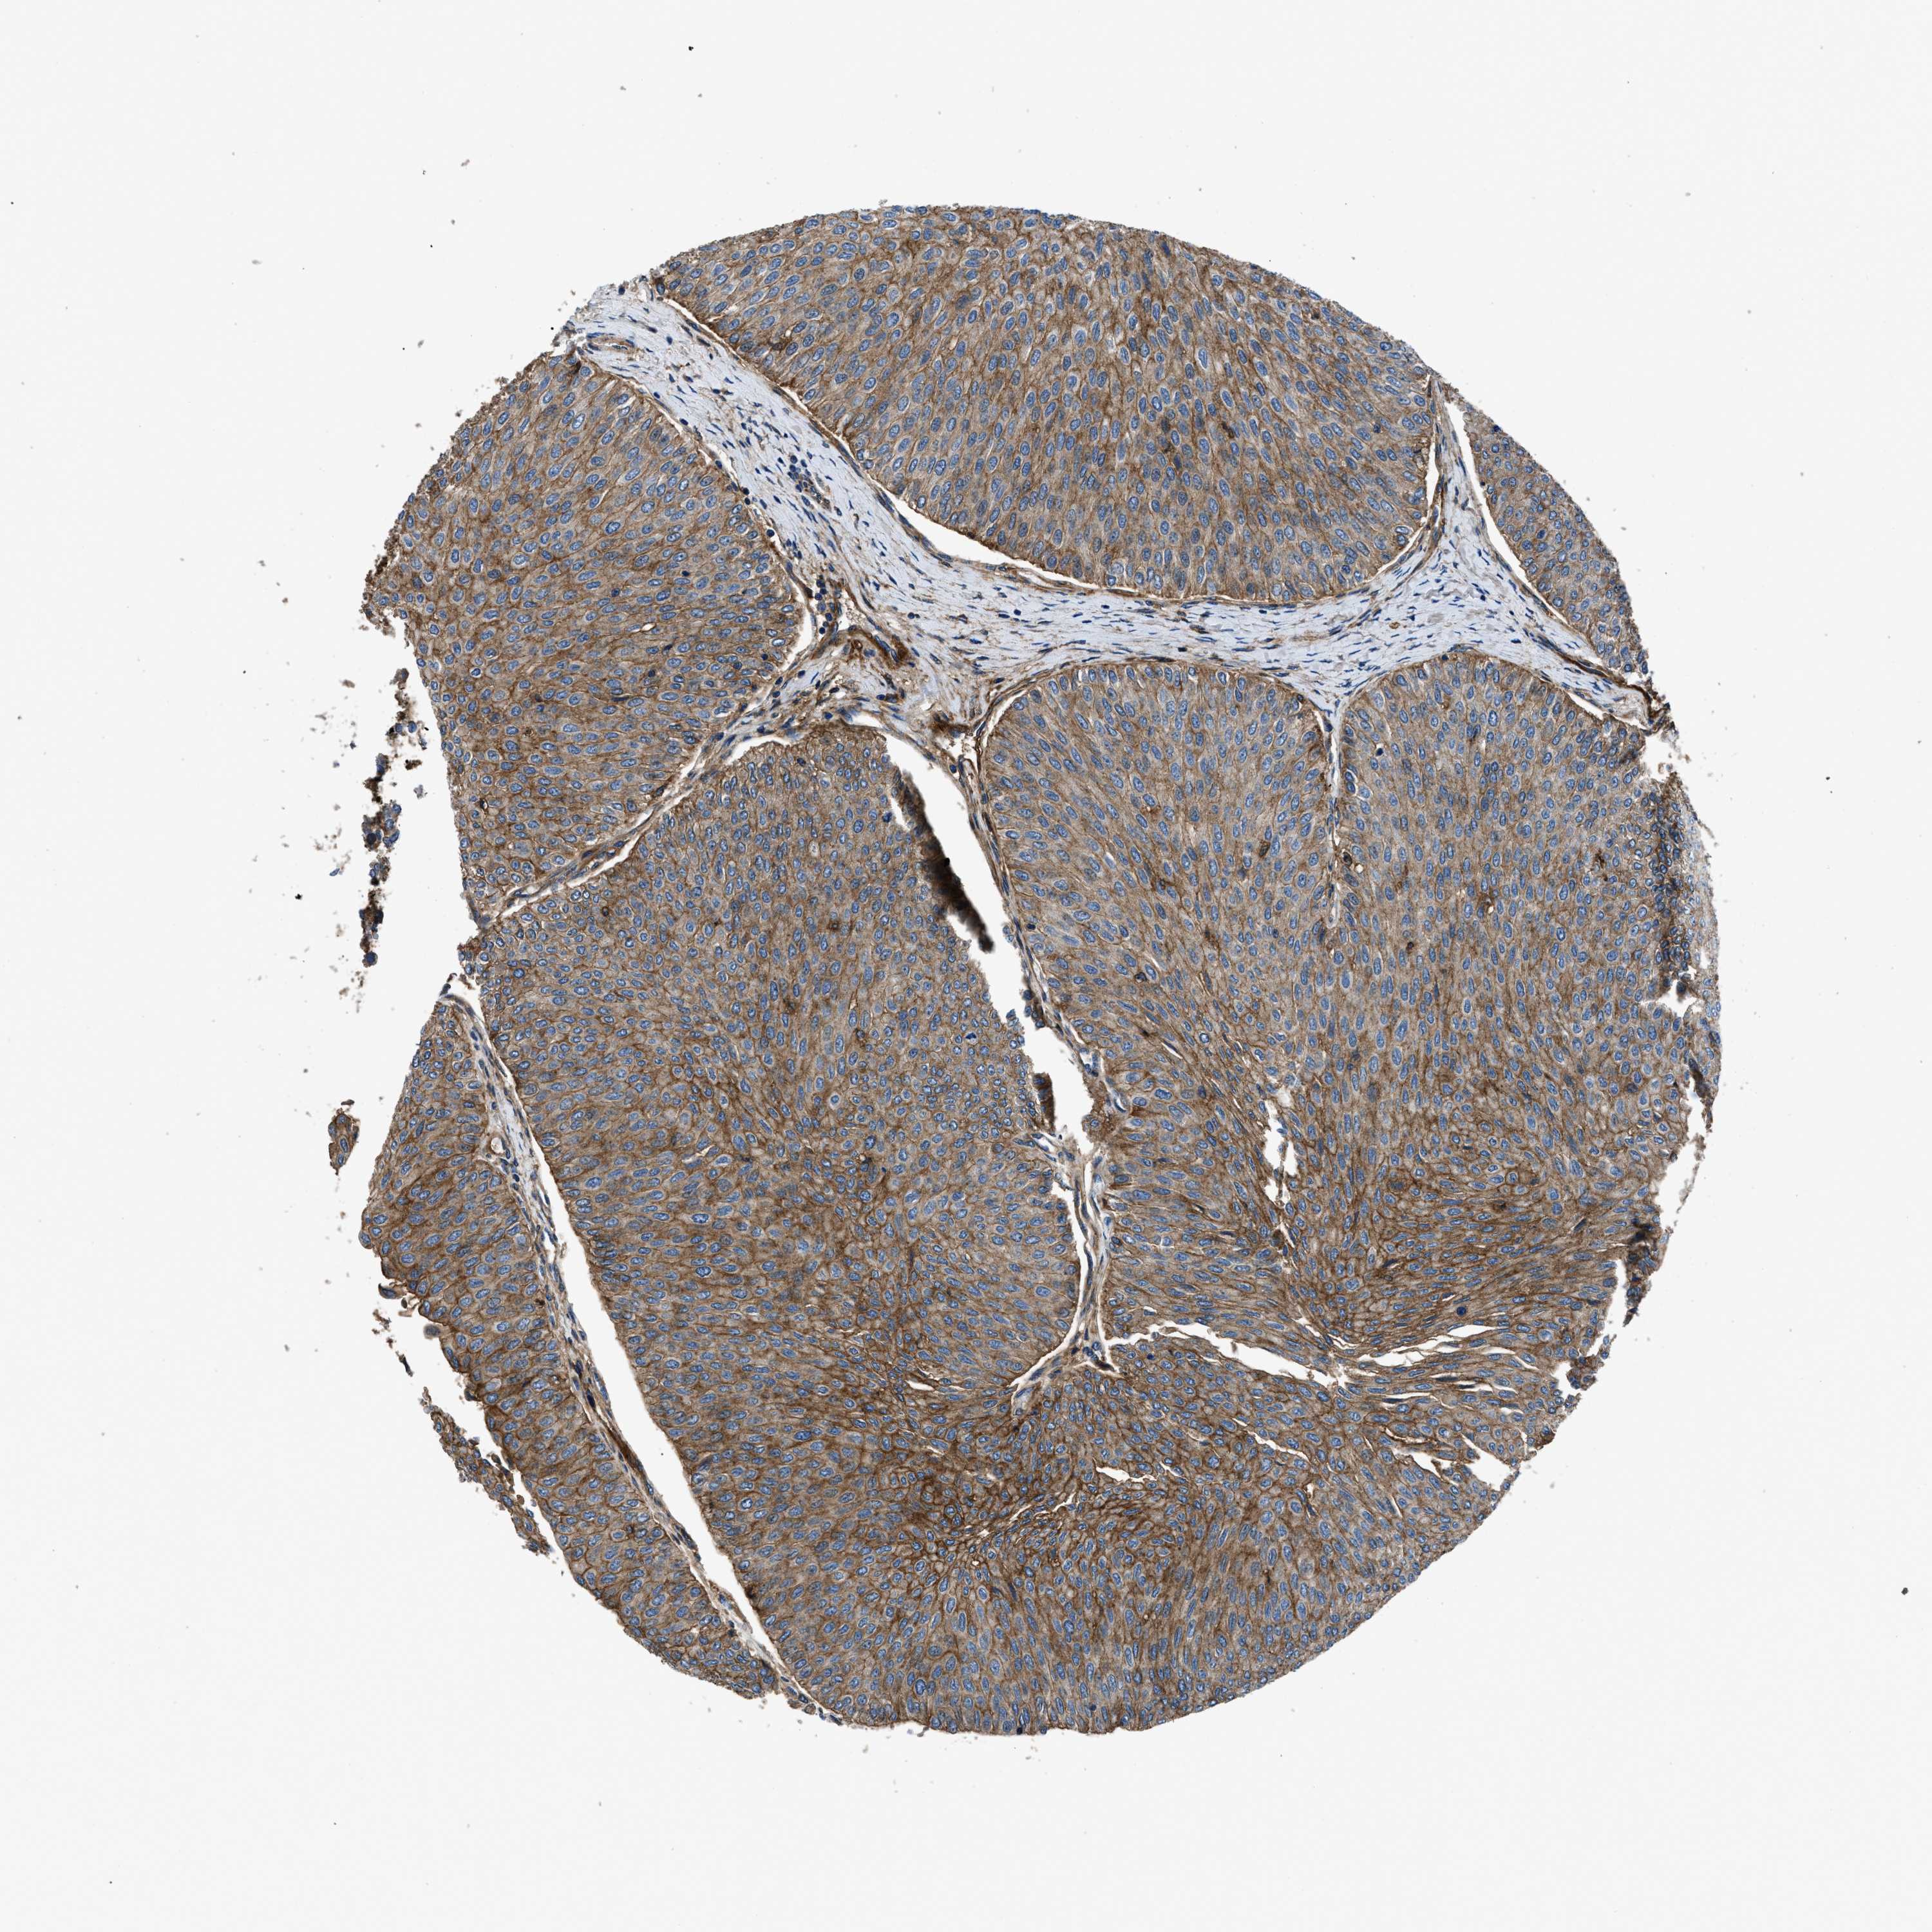

UROTHELIAL CANCER - Protein expressioni

A mouse-over function shows sample information and annotation data. Click on an image to view it in a full screen mode. Samples can be filtered based on level of antibody staining by selecting one or several of the following categories: high, medium, low and not detected. The assay and annotation is described here.

Note that samples used for immunohistochemistry by the Human Protein Atlas do not correspond to samples in the TCGA dataset.

Antibody stainingi

Antibody staining in the annotated cell types in the current human tissue is reported as not detected, low, medium, or high, based on conventional immunohistochemistry profiling in selected tissues. This score is based on the combination of the staining intensity and fraction of stained cells.

Each image is clickable and will lead to virtual microscopy that enables deeper exploration of all samples and also displays staining intensity scores, fraction scores and subcellular localization as well as patient and tissue information for each sample.

Antibody HPA009285

Antibody HPA017139

Antibody CAB017826

Urothelial carcinoma, Low grade

Urothelial carcinoma, High grade